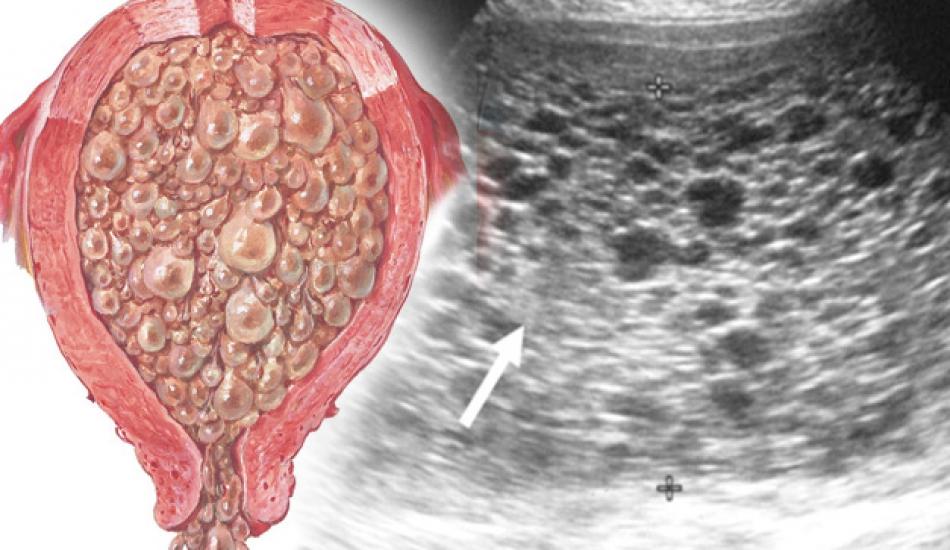

Halk arasında 'Üzüm gebeliği' olarak bilinen Mol gebelik, kromozomların anormal bir şekilde dizilmesiyle ortaya çıkarak sağlıksız gelişen bir hamilelik türüdür. Anne adayında sıklıkla görülen mide bulantısı, yüksek tansiyon, kalp atışındaki düzensizlik, ciddi kramp ve terleme gibi belirtiler mol gebeliğin işaretleri arasında olabilir. Döllenme sırasında genetik hatanın sonucunda rahimde anormal dokunun büyümesiyle sağlıklı plasenta yerine açık üzüm salkımı görünümüne benzer bir doku yığını görülür. Buradan da yola çıkarak üzüm gebeliği olarak nitelendirdiğimiz mol gebelik ile ilgili merak edilenleri sizler için derledik. Peki hamilelikte oluşan üzüm gebeliği tam olarak nedir? İşte mol gebelik...

Kadındaki yumurta hücresi döllenme sırasında tek bir tane spermi içine alır ve diğer spermlerin içeri girmesini engeller. İki spermin içeri girmesi hamilelik durumunu değiştireceği için anormal embriyo sonucunda çok sayıda keselerden oluşan bir yapı görülür. Bu yapıya ise Mol gebelik denir. Sosyoekonomik düzeyi düşük kimselerde ve sağlıksız beslenenlerde daha yaygın görülme ihtimali olan üzüm gebelik 20 yaş altı ve 40 yaş üstü anne adaylarının 1500’ünden 1'inde görülür.

Normal hamilelik zamanından daha fazla bulantısı olur. Kusma ve tüylenme mol gebeliğin önemli sinyallerindendir. Kesin tanı için ultrason görüntüsü şarttır.